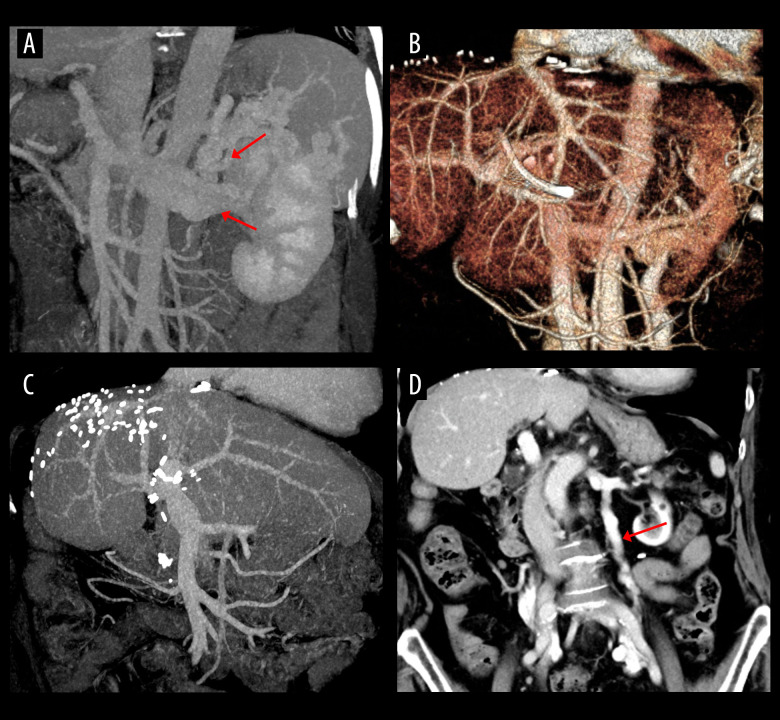

背景 大型自发性脾肾分流(SSRS)的持续存在会导致成人活体肝移植(LDLT)中门静脉血流窃取而导致移植失败;因此,有必要阻断 SSRS 以确保充足的门静脉血流。材料与方法 我们在之前的前瞻性研究基础上进行了一项为期20年的回顾性观察随访研究,以评估结扎左肾近端静脉(LRV)后的长期疗效。2001 年 10 月至 2005 年 1 月期间,44 名肝硬化患者接受了 LDLT 和 LRV 结扎术。对这些患者进行了随访,直至 2024 年 4 月或患者死亡。结果 结扎 LRV 后门静脉流量明显增加。40 名患者在 LDLT 术后肾功能恢复良好。18名患者死于癌症复发(6人)、肺炎(3人)和其他原因(9人),因此患者的1年、5年、10年和20年总生存率分别为95.5%、86.4%、81.8%和59.1%。未观察到左肾孤立性萎缩。有 20 名患者的 SSRS 已完全消除,但另外 20 名患者至今或在患者死亡时仍有不同程度的可识别 SSRS。另外 4 名患者的 LRV 再次开放,形成了较大的 SSRS,其中 2 人因静脉曲张出血控制而进行了逆行经静脉阻塞,另外 2 人因门静脉血流增强而进行了逆行经静脉阻塞。结论 本研究表明,LRV 结扎是控制 SSRS 的一种安全有效的方法。目前,直接结扎 SSRS 是首选,但在无法直接进入 SSRS 的情况下,LRV 结扎仍不失为一种良好的治疗选择。

BACKGROUND Persistence of large spontaneous splenorenal shunt (SSRS) can result in graft failure in adult living donor liver transplantation (LDLT) due to portal flow steal; thus, it is necessary to block SSRS to ensure sufficient portal blood flow. MATERIAL AND METHODS We performed a retrospective 20-year observational follow-up study subsequent to a prior prospective study to evaluate the long-term outcomes following ligation of the proximal left renal vein (LRV). Between October 2001 and January 2005, 44 liver cirrhosis patients underwent LDLT with LRV ligation. These patients were followed up until April 2024 or patient death. RESULTS Portal flow was significantly increased after LRV ligation. Renal function recovered uneventfully after LDLT in 40 patients. Eighteen patients died due to cancer recurrence (n=6), pneumonia (n=3), and other causes (n=9), thus 1-, 5-, 10-, and 20-year overall patient survival rates were 95.5%, 86.4%, 81.8%, and 59.1%, respectively. Solitary atrophy of the left kidney was not observed. SSRS was completely resolved in 20 patients, but the other 20 patients showed persistently identifiable SSRS of variable extents to date or at patient death. The LRV was reopened to make large SSRS in another 4 patients, in which retrograde transvenous obliteration was performed in 2 for variceal bleeding control and in another 2 for portal flow augmentation. CONCLUSIONS This study demonstrated that LRV ligation is a safe and effective method to control SSRS. Currently, direct ligation of the SSRS is preferred, but LRV ligation still can be a good therapeutic option when direct access to SSRS is not feasible.